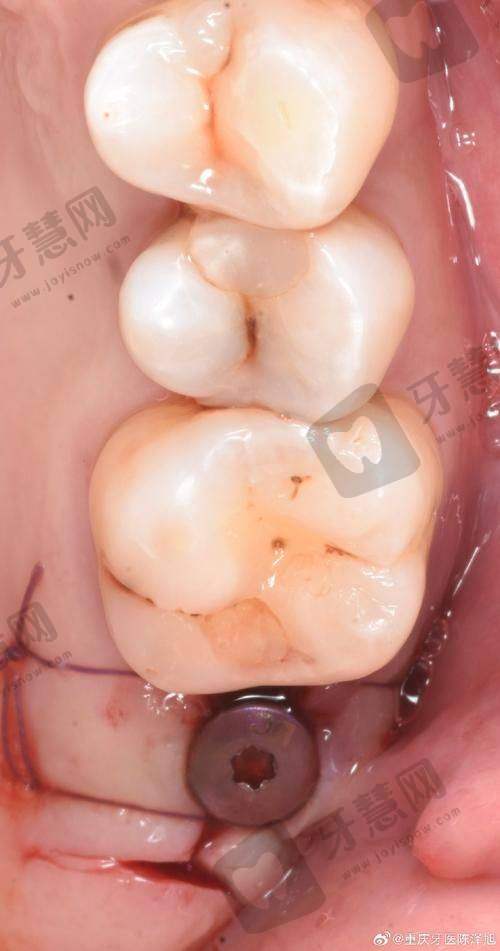

3. 沈阳沈美口腔价格表之种植牙攻略:4076元起实现“牙齿重生”

缺牙的中老年朋友注意啦!沈美口腔的种植牙套餐性价比惊艳:

韩国登腾种植体 + 爱尔创全瓷冠4076元起:进口材料 + 全瓷牙冠,坚固耐用,邻居张阿姨种完3年,啃排骨都没问题;

美国皓圣Hiossen种植牙7106 - 7903元:适合牙槽骨条件较好的人群,手术时间短,当天就能戴临时牙;

微创即刻种植牙8739 - 15077元:拔完牙立刻种,避免二次创伤,特别适合怕痛的朋友。

划重点:国产清水种植牙4290 - 6142元,预算有限的姐妹可以考虑,医生说成功几率和进口品牌不相上下哦!